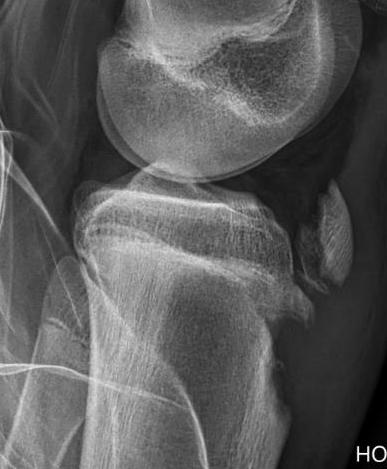

CT / MRI scan

CT scan - ensure fracture doesn't involve the physis / disrupt articular surface

Type IB

Type IIB

Type III

Comminuted Type III